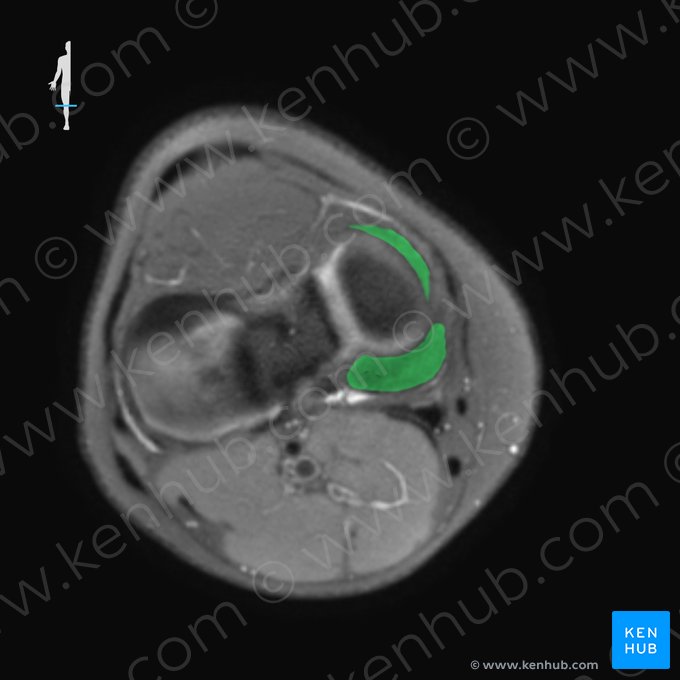

Knee (MRI)

One sequence that is very useful to evaluate the knee joint - and most musculoskeletal structures - is the proton density-weighted sequence, also known as PD-weighted. PD images usually show similar signal intensity on fluids and fat, that normally appear as a light gray. This helps identifying this sequence.

The images below show the main structures that can be identified in the knee MRI using PD-weighted sequences.